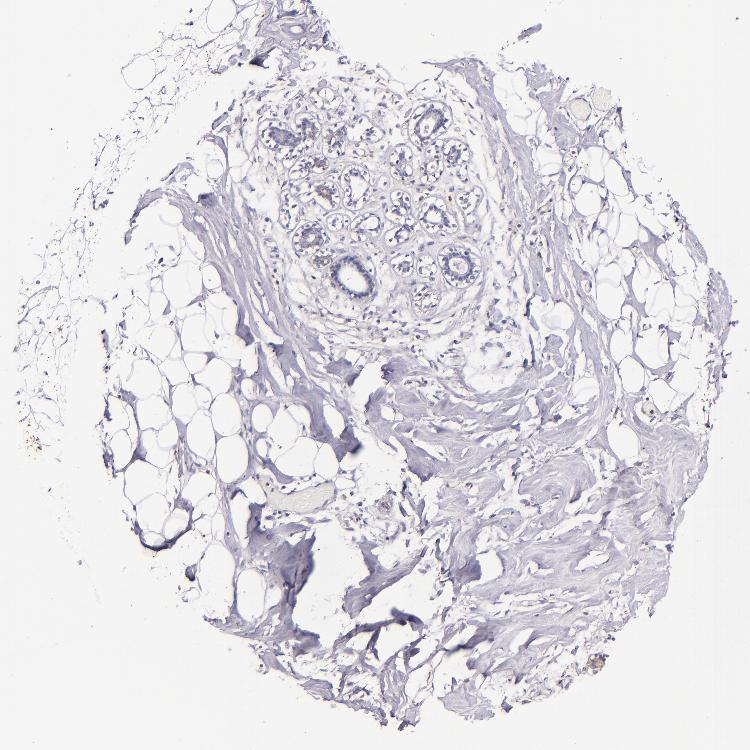

BREAST - Antibody stainingi

Antibody staining in the annotated cell types in the current human tissue is reported as not detected, low, medium, or high, based on conventional immunohistochemistry profiling in selected tissues. This score is based on the combination of the staining intensity and fraction of stained cells.

Each image is clickable and will lead to virtual microscopy that enables deeper exploration of all samples and also displays staining intensity scores, fraction scores and subcellular localization as well as patient and tissue information for each sample.

Antibody HPA054437Antibody HPA058511Antibody CAB002776Antibody CAB015122

Adipocytes Not detectedNot detectedNot detectedNot detected

Glandular cells Not detectedNot detectedLowMedium

Myoepithelial cells Not detectedNot detectedNot detectedNot detected